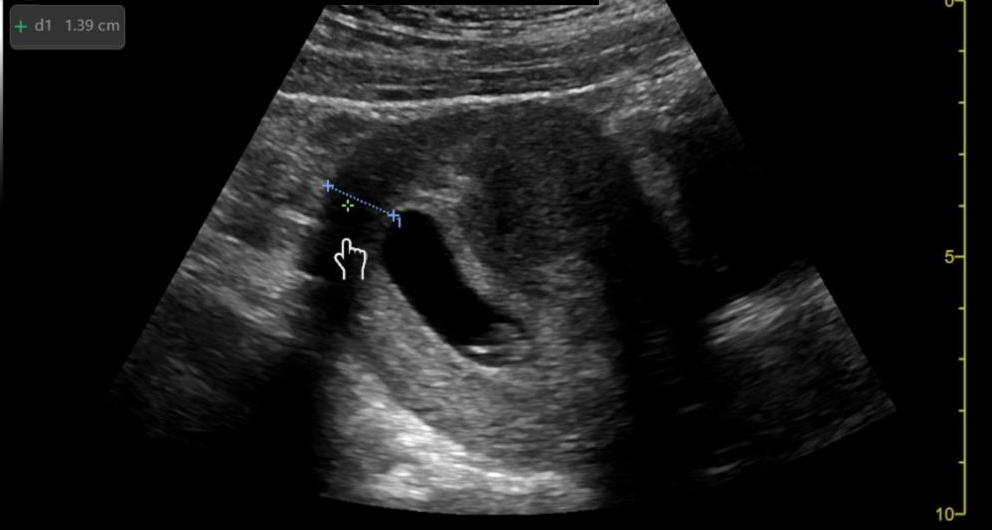

Image 1: Intussusception short axis diameter measurements.